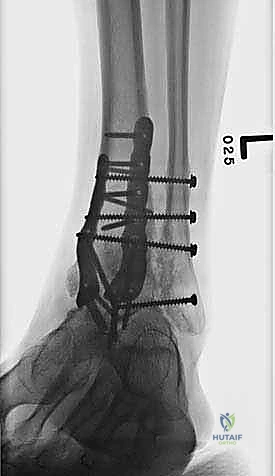

تثبيت مفصل الكاحل، أو "دمج الكاحل" (Ankle Fusion)، هو إجراء جراحي عالي التخصص يهدف إلى تحويل مفصل الكاحل المريض والمؤلم إلى كتلة عظمية واحدة صلبة وغير متحركة. الفلسفة الطبية وراء هذا الإجراء بسيطة وفعالة: "مفصل ثابت وبدون ألم أفضل بكثير من مفصل متحرك يسبب ألماً مبرحاً".

- تثبيت ميكانيكي حيوي أقوى: يتيح المدخل الأمامي وضع شريحة معدنية (Anterior Plate) على الجانب الأمامي للمفصل. من الناحية الميكانيكية الحيوية (Biomechanics)، يعتبر الجانب الأمامي هو "جانب الشد" (Tension side) أثناء المشي. وضع الشريحة هنا يوفر تثبيتاً فائق القوة ويقلل من معدلات عدم الالتئام.

- التخطيط الجراحي الرقمي: باستخدام صور الأشعة المقطعية، يقوم الدكتور هطيف بتخطيط الجراحة على الكمبيوتر لاختيار حجم المسامير والشرائح المناسبة بدقة مليمترية.

خطوات جراحة تثبيت مفصل الكاحل الأمامي بالتفصيل (Step-by-Step Surgical Procedure)

تُجرى العملية تحت التخدير العام أو النصفي (الشوكي)، وتستغرق عادةً بين ساعتين إلى ثلاث ساعات، وتتطلب دقة ومهارة فائقتين. إليكم الخطوات الجراحية كما ينفذها الأستاذ الدكتور محمد هطيف: